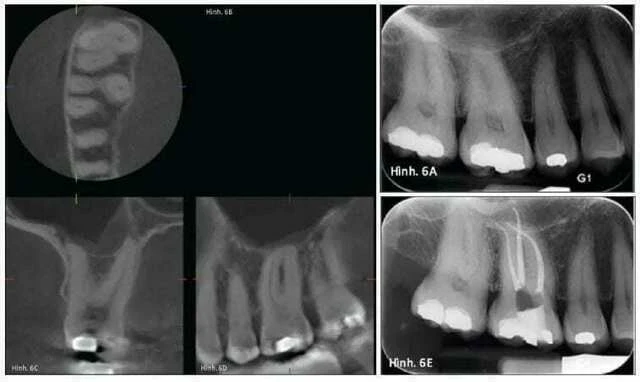

Bệnh nhân xuất hiện viêm tuỷ không hồi phục ở răng số #3, được xác nhận bằng thử nghiệm lạnh và nhiệt (phản ứng đau kéo dài). Chụp X quang thông thường cho thấy giải phẫu ống tuỷ gần – ngoài rất cong, với giải phẫu ống tuỷ xa ngoài và ống trong tương đối thẳng (Hình 6A).

Hình ảnh CT Accuitomo đã tiết lộ một tình tiết khác, nhắc nhở nhà lâm sàng cẩn thận trong quá trình điều trị (Hình 6B.). Thông tin quan trọng đầu tiên là chiếc răng này chỉ có ba ống tuỷ (Hình 6C).

Phần thông tin quan trọng thứ hai là độ cong của ống tuỷ gần ngoài thực sự ấn tượng (Hình 6D). Thông tin thứ ba đã cứu tôi và chiếc răng bệnh nhân khỏi bị gãy trâm quay khi sửa soạn đó là nó tiết lộ một ống tuỷ có độ cong nghiêm trọng – mà khi nhìn theo hướng phía ngoài sẽ bị che khuất đi (Hình 6E). Nhờ vậy việc điều trị được tiến hành nhanh chóng và chắc chắn với kết quả đặc biệt (xin lỗi, nhưng sự thật là như vậy) (Hình 6E).